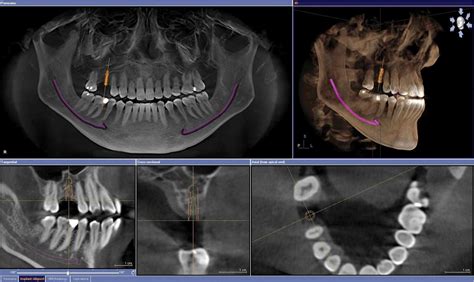

Un TAC dental consiste en una exploración con rayos X para obtener imágenes de las estructuras dentales, tejidos blandos, nervios y huesos de la cabeza. Con los datos obtenidos, el doctor podrá utilizar las potentes herramientas digitales que ofrece el software para realizar un diagnóstico más exacto.

Existen dos tipos de tomografía computarizada (TC): la TC convencional y la TC de haz cónico. Para realizarte el TAC dental tendrás que sentarte y mantener una posición firme (para evitar movimientos y obtener resultados más precisos) apoyando tu barbilla en el soporte habilitado. Después, el brazo rotatorio girará 360º sobre la cabeza, de modo que tanto el generador de rayos X como el detector que genera las imágenes rotan de manera simultánea.

La tecnología Cone Beam ha supuesto para la comunidad dental la posibilidad de acceder con facilidad a la imagen multiplanar en los tres ejes del espacio. En un solo giro i-CAT proporciona múltiples imágenes y reconstrucciones tridimensionales (3D) precisas de cualquier área anatómica de interés. La resolución de la imagen es isotrópica, igual en las tres dimensiones del espacio, dando como resultado imágenes sin distorsión ni magnificación a escala 1:1.

La calidad de la imagen depende significativamente de la calidad del sensor utilizado. El sensor Flat Panel, al contrario que los detectores CCD y los sistemas de intensificación de imagen no crean distorsiones ni artefactos de la imagen captada.